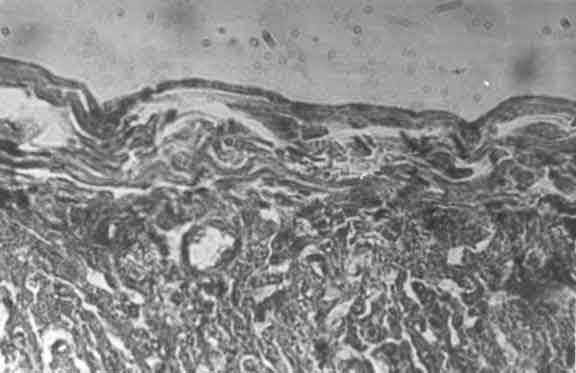

Во всех случаях при морфологических исследованиях сердца отмечались значительные изменения сосудов различного калибра: неравномерность кровенаполнения, полнокровие с явлениями стаза и вторичный парез артериальных сосудов. Отмечались многочисленные кровоизлияния. Эти растройства кровообращения встречались повсеместно, но чаще в слоях близких к эндокарду, субэндокардиально и превалировали у детей с электрокардиографическими признаками нарушения внутрижелудочковой проводимости по ножкам пучка Гиса с преимущественной локализацией в субэндокарде правого желудочка (рис. 6).

Рис. 6. Субэндокард правого желудочка. Ув. x14. Выраженный отек, разволокнение. Неравномерное кровенаполнение, кровоизлияния.

Имевшие место у всех детей периваскулярный отек, набухание эндотелиальных клеток и их слущивание свидетельствовали о глубоких повреждениях сосудистой стенки [7]. Отмеченные нарушения носили мозаичный характер, соседние с ними неизмененные области, по-видимому, компенсировали в функциональном плане имеющиеся морфологические нарушения. Вследствие этого в клинической картине поражение сердечно-сосудистой системы не было манифестным.